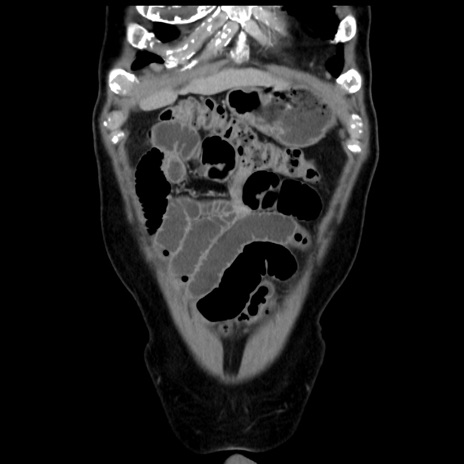

症例16(冠状断像)

【症例】 70歳代男性

【主訴】 腹痛、嘔吐

【現病歴】 約1ヶ月前より間欠的に腹痛と嘔吐あり、当院消化器内科を受診したところCTで多発する肝臓のLDAを指摘され、精査中であった。以降は消化器症状は安定していたが、2日前より嘔気と腹痛があり、同日より排便・排ガスが消失した。改善認めず、 本日、救急外来を受診した。

【既往歴】 大腸ポリープ切除後。

【身体所見】意識清明・会話良好、BT 36.3℃、BP 127/80mmHg、 P 80bpm、腹部:膨満あり、平坦・軟、上腹部正中および下腹部正中に圧痛あり、反跳痛なし、筋性防御なし。

【データ】WBC 7200、CRP 0.77